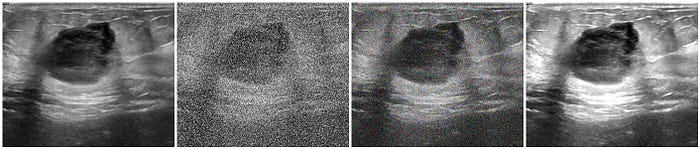

Brightness & Contrast

Brightness and contrast is probably the most basic type of data augmentation technique that you can choose. For medical images, changes in brightness and contrast should be subtle to avoid distorting the image's diagnostic value. The goal is to enhance visual perception without introducing artificial features.

According to IMAIOS, a well-known medical image tool database company for health practitioners, changes to brightness should be in random intervals of [-0.1 : 0.1] and changes in contrast should range between [0.8 : 1.2]. What this means is that if the default value of the brightness and contrast of the image is 1, then data augmentation for brightness should be done in the range of [0.9 : 1.1] and contrast should be done as written above.

To acquire and implement this technique in a python setting, we will use PyTorch and it's torchvision library. Key component to takeaway from this code is the transforms.ColorJitter function. It applies color jitter transformations to the image, which can be brightness, contrast, hue, and saturation. In our case, it randomly adjusts the brightness within the specified range of (0.9, 1.1) and contrast between (0.8, 1.2).

display(img)Contrast